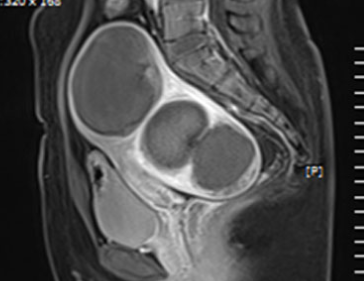

• 시술 전

시술 후